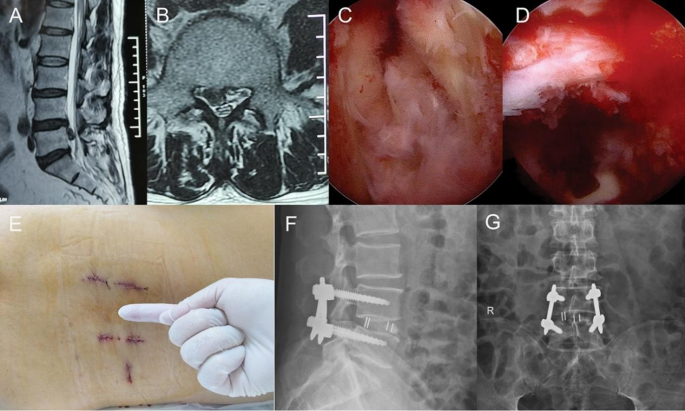

Endo-TLIF: After general anesthesia, the patient was prone on the operating table. Fluoroscopy was used to locate the target intervertebral space, the posterior midline, and the pedicle surface projection. Initially, four percutaneous guide needles were inserted. The expanding catheter was used to separate the soft tissue, and then, the working channel of the spinal endoscopy was placed. After positioning the spinal endoscope, ablation exposed the lateral anatomy of the facet joint, identifying the tip of the facet joint and the pedicle. At the facet joint space, the annular saw was used to removed part of the facet joint, exposing the endpoints of the ligamentum flavum on both the cranial and caudal sides, and removing part of the lamina to the base of the spinous process. After bony decompression and clarifying the structure of the ligamentum flavum, the ligamentum flavum was removed to expose the dural sac and nerve roots. After revealing the lateral structure of the traversing root, an intervertebral disc guide rod was inserted to protect the inner side of the dural sac, placing an expandable elastic channel (ZLIF channel) into the disk space, The cartilaginous endplate was treated using an endplate scraper, exploring the endplate surface under the scope. Autologous bone and artificial bone were inserted into the intervertebral space, and a cage of appropriate size was inserted through the channel. After satisfactory positioning under fluoroscopy, the endoscope was removed. Four percutaneous pedicle screws were inserted, and rods were placed for fixation. Irrigation and suture were performed (Fig. 1).

Endo-TLIF: A 56-year-old male complains of chronic lower back pain for 3 years, with radiating pain and weakness in the right lower limb for 3 weeks. Preoperative magnetic resonance images showing severe L4/L5 disc herniation (A and B); Endoscopic view after the foraminoplasty showed decompressed L5 nerve and resected L4/5 disc (C and D); (E) Skin incisions. Postoperative day 2 lumbar spine AP and lateral view (F and G).